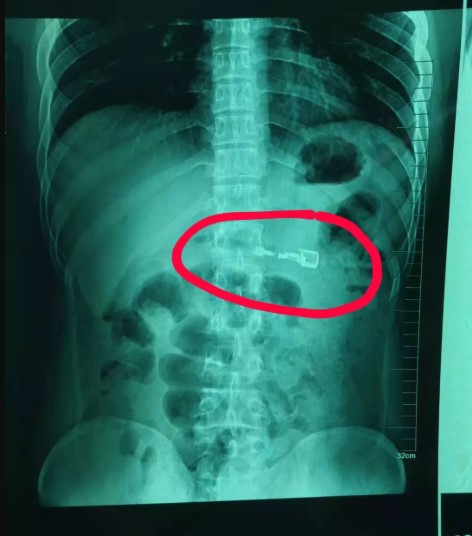

Un joven de 23 años de edad fue intervenido de emergencia luego de que estando ebrio se tragara un encendedor.

Médicos del Hospital Shenyang Número Cinco de China indicaron que el paciente corrió con mucha suerte, pues de esperar más tiempo, el artefacto pudo explotarle dentro.

Allí, descubrieron que los jugos gástricos del joven habían erosionado el artefacto, por lo que el combustible pudo liberarse dentro de su estómago en cualquier momento.

Para evitar mayores daños, los doctores realizaron una gastroscopia a Li, quien se encuentra en estable.